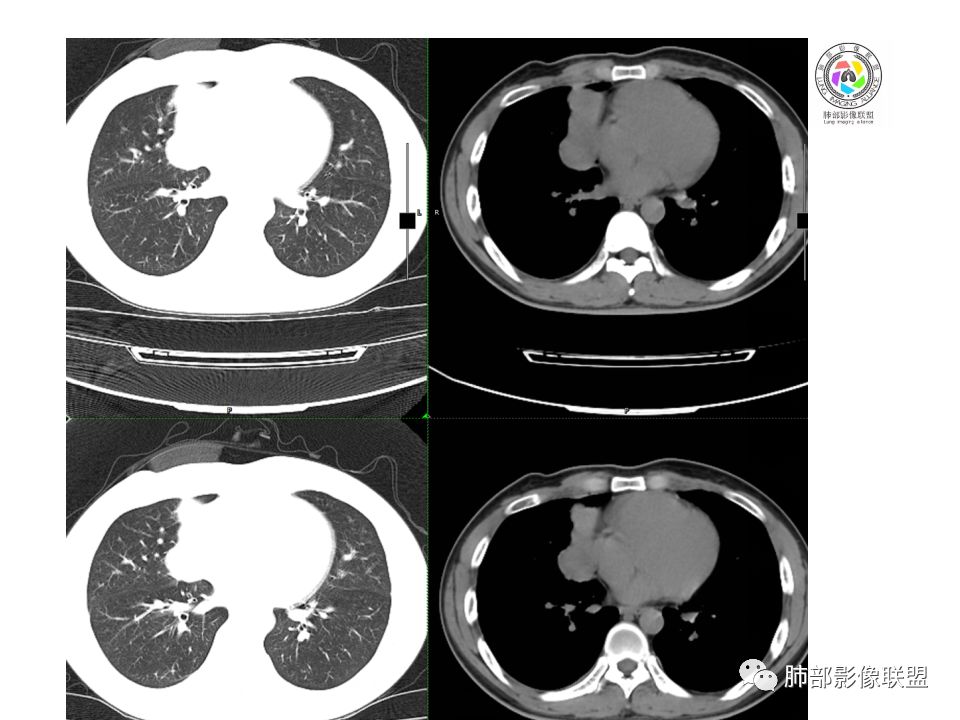

晨读:前纵隔占位,密度不均,沿着右侧纵膈延伸到肺门水平,周围支气管推移,大血管向内推移。临床有重症肌无力,考虑胸腺瘤可能,鉴别淋巴瘤。

右前纵膈肿块,偏一侧生长,形态欠规则,密度不均匀,其内可见小点状钙化,双肺多发小叶中心结节及钙化灶,右侧胸膜增厚(有陈旧性结核可能),青年男性(27岁),没有增强,考虑,1,前纵隔生殖细胞瘤2,精源细胞瘤

右前上纵隔占位,瘤肺交界面清楚,提示纵隔来源,其内有点状钙化,右侧胸腔积液,有临床症状,年龄轻,考虑生殖来源可能,胸腺瘤待排,请结合临床相关检查或CT增强进一步检查。

前纵隔占位,伴点状钙化;上腔静脉后移位。伴右胸膜局限性增厚,临床有重症肌无力,病人年轻,考虑胸腺瘤可能,鉴别生殖源性肿瘤。

右前纵隔占位,有分隔`低密度、点状钙化,边缘光滑,侵袭心包不明确,伴右胸少量积水,考虑恶性,生殖源性可能大,有视物不清,是否脑转移待查。建议HCG丶AFP检查。鉴别1:胸腺瘤、癌,30一40岁以下,少见,但有眼脸下垂,肌无力,待排除。2:淋巴瘤:侵袭性不强,有点状钙化,不支持。3:畸胎瘤:有低密度丶钙化,建议增强进一步明确。4:神经源性:一般后纵隔常见,不支持。5:LCD:症状少见,可以有树枝状钙化,浆细胞型可以有低密度,增强进一步明确

没有增强,好像两个病灶,上方三角形的像是胸腺增生。下方肿块,没有增强显得更难了,微钙化,轻度分叶,像有坏死低密度影,右侧少量胸水,胸膜受侵.,有视物模糊眼睑下垂。考虑胸腺瘤B1型及以上、B2型可能或生殖细胞瘤

前纵隔右区占位性病变,上区与胸腺延续,下区呈分叶状,尽管年龄<30还是首先考虑胸腺瘤,侵袭性可能性大(眼睑下垂不知是否有关)。鉴别主要是生殖细胞类肿瘤,主要是精原细胞瘤。另左肺上叶结核球,右侧胸腔积液,需除外结核性胸膜炎和转移

右前纵隔肿块,边界清楚,密度欠均匀,内似有分隔和低密度区,似有多结节融合,几乎从上到下,年龄较轻,不是胸腺瘤好发年龄,但却有视物模糊,眼睑下垂症状,考虑淋巴瘤?鉴别胸腺瘤?结核?

右前上纵膈肿块,内有点状钙化和少许小片状坏死,局部边界似欠清,右侧胸膜腔少量积液,年轻男性,小于30岁,有重症肌无力,虽然年龄偏轻,仍先考虑胸腺瘤,代排生殖源性肿瘤

晨读前纵隔肿块,偏右侧,密度不均,见点状钙化灶及分隔状低密度影。胸腺瘤>生殖细胞瘤>淋巴瘤

前中纵隔(胸腺癌区)不规则肿块,密度不均,有坏死区、点状钙化,边缘不会整肿块偏向右侧,向心包流注感,右胸腔少量积水。患者27岁,重症肌无力表现。